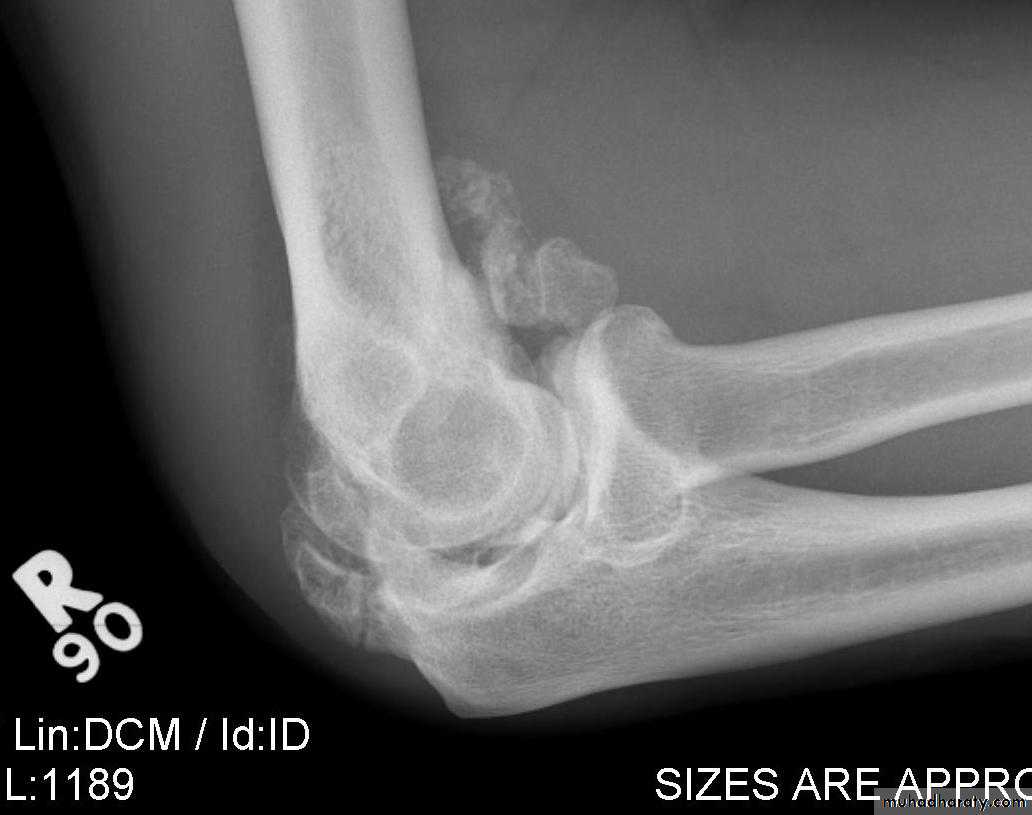

Myositis ossificans :

Heterotopic ossification in the musclesCommon sites : elbow or a blow to the brachialis, deltoid or quadriceps. especially in unconscious or paraplegic patients

x-ray may show fluffy calcification in the soft tissues.

The joint should be rested in the position of function until pain subsides; gentle active movements are then begun.

Months later, when the condition has stabilized, it may be helpful to excise the bony mass.

Indomethacin or radiotherapy should be given to help prevent a recurrence.